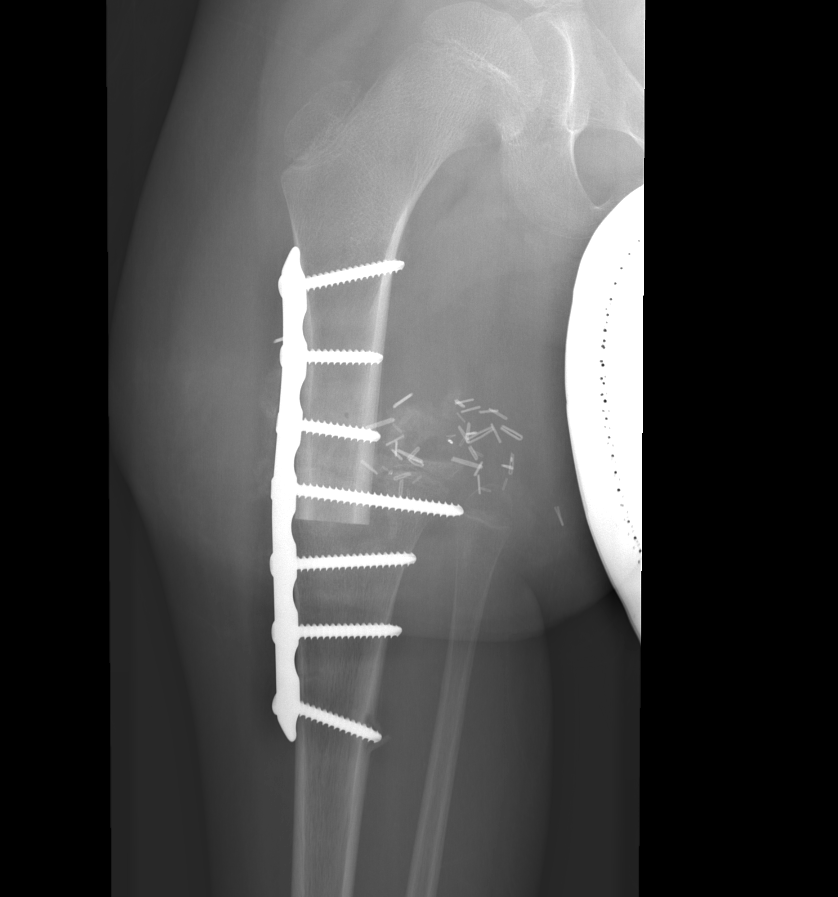

Section 1 Submit Findings CB1550 Findings Skeletal Survey - Technique Check Skull AP/Lat Yes No Cervical and Thoracolumbar spine Yes No Chest X-Ray Yes No Ribs – Left/Right Oblique Yes No Abdominal X-Ray Yes No Pelvis with both hips Yes No Bilateral Humerus, Forearm, Hand Yes No Bilateral Femur, Tibia/fibula, feet Yes No Any additional lateral views of the extremities Yes No The exam is over or under penetrated. Yes No The exam may or may not be limited by overlying structures or soft tissues, body habitus, patient positioning, support devices, or motion. Yes No The area of concern is indicated by the patient, technologist, or care provider. Yes No The area of concern is included on the exam. Yes No Soft Tissues There is soft tissue swelling, indistinctness of fat/muscle planes, gas, or laceration in the area of clinical concern. Yes No There is an effusion, fat pad displacement, or fat fluid level. Yes No There is a radiodense or lucent foreign body. Yes No There are other densities, calcifications, post-surgical changes, or support devices in the soft tissues. Yes No Any support lines/tubes. Yes No Bone There is a break or interruption of the continuity of the cortical or cancellous bone. Yes No There is overriding of the trabeculae with apparent sclerosis. Yes No There is displacement of a fracture fragment. Yes No There is bowing of the bone in addition to the fracture at the apex of the bowed bone concerning for the greenstick. Yes No There is a spiral fracture of the leg concerning for toddler’s fracture. Yes No There is abnormal angulation or bulging of the cortical surface relative to the normal cortex which could be from a buckle or torus fracture. Yes No There is a displaced fragment which may be from avulsion by a tendon, ligament, or joint capsule or from a comminuted or other fracture. Yes No The stress trabeculae or other trabeculae of the cancellous bone are interrupted or otherwise abnormal. Yes No There is subperiosteal or endosteal reaction which could indicate a healing or subacute fracture or other abnormality. Yes No There is hard/soft callus formation. Yes No There is remodeling of the bone. Yes No There is a corner fracture or metaphyseal lesion that could be from nonaccidental trauma. Yes No There are multiple fractures of different ages. Yes No There are vertebral body/spinous process fractures. Yes No There are rib fractures. Location - posterior or lateral. Yes No There is scapular/sternal fracture. Yes No There are fractures of the digits. Yes No There are wormian bones. Yes No There are intrasutural bones. Yes No There is metaphyseal abnormality (lucencies, increased density, erosion) which may be from something other than injury such as stress, metabolic disease (e.g. rickets with loss or distortion of the zone of the provisional calcification), neoplasm (e.g. leukemia), heavy metals, inflammation, or infection. Yes No There are metaphyseal spurs. Yes No There are bony deformities involving multiple bones. Yes No The bones are gracile. Yes No There are non-healing fractures. Yes No There is/are focal or multifocal lytic/lucent, blastic/sclerotic or mixed density lesion(s) or other abnormality. Yes No Overall bone density is increased or decreased with or without thinning or thickening of the cortical or cancellous bone. Yes No Growth plates, ossification centers, apophyses The growth plate(s) is/are abnormal. Yes No There is widening of the physis from a fracture with or without displacement of the epiphysis (Salter-Harris I). Yes No There is a fracture through the physis which then extends into the metaphysis with or without angulation or displacement (S-H II). Yes No There is a fracture through the physis which then extends into the epiphysis and is intra-articular, with or without angulation or displacement (S-H III). Yes No There is a fracture through the metaphysis, physis, and epiphysis which extends into the joint space with or without angulation or displacement (S-H IV). Yes No There is narrowing of the physis from a compression fracture (S-H V). Yes No The apophysis, epicondyle, secondary ossification center, or accessory ossicle is displaced or otherwise abnormal. Yes No The ossification centers are underdeveloped. Yes No Joints and alignment There is an effusion, fat pad displacement, or fat fluid level. Yes No The epiphysis or subchondral bone is fractured, interrupted, flattened, compressed, impacted, displaced, or otherwise abnormal. Yes No There is an intra-articular loose body or chondrocalcinosis. Yes No The joint is widened, narrowed, dislocated, malaligned, or incongruent. Yes No There is pseudoarthrosis. Yes No Other findings There are developmental changes or other anatomic variants or other existing conditions that may or may not be contributing to symptoms which can or should be further evaluated non-emergently or are otherwise incidental. Yes No The remainder of the exam is abnormal for age. Yes No The lungs show focal airspace opacity. Yes No There is pneumothorax. Yes No There is organomegaly. Yes No There is intra-abdominal calcification. Yes No There is displacement of the bowel loops. Yes No There is free intraperitoneal air. Yes No The bowel loops are dilated/obstructed. Yes No There is paraspinal soft tissue abnormality. Yes No